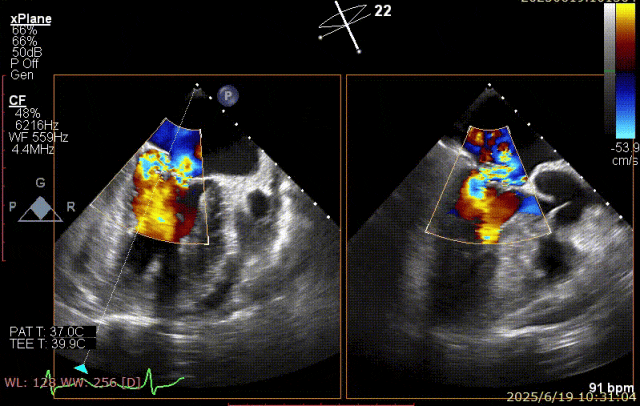

术前超声

患者术前 TEE 可见 P3 区脱垂二尖瓣环前后径(AP)约 37 mm,CC 径约 41 mm,瓣叶无明显钙化及裂隙,后瓣瓣尖探及一长约 9 mm 短带样回声漂附,二尖瓣口面积约 5.3 cm²。

经我院心脏超声检查提示:左房室增大伴二尖瓣后瓣脱垂(P3 区,腱索断裂)并重度关闭不全(Carpentier IIb 型,反流分级 4+);符合高血压性心脏病改变;少至中等量心包积液;左室舒张功能降低,收缩功能测定在正常范围并呈假性高排表现。